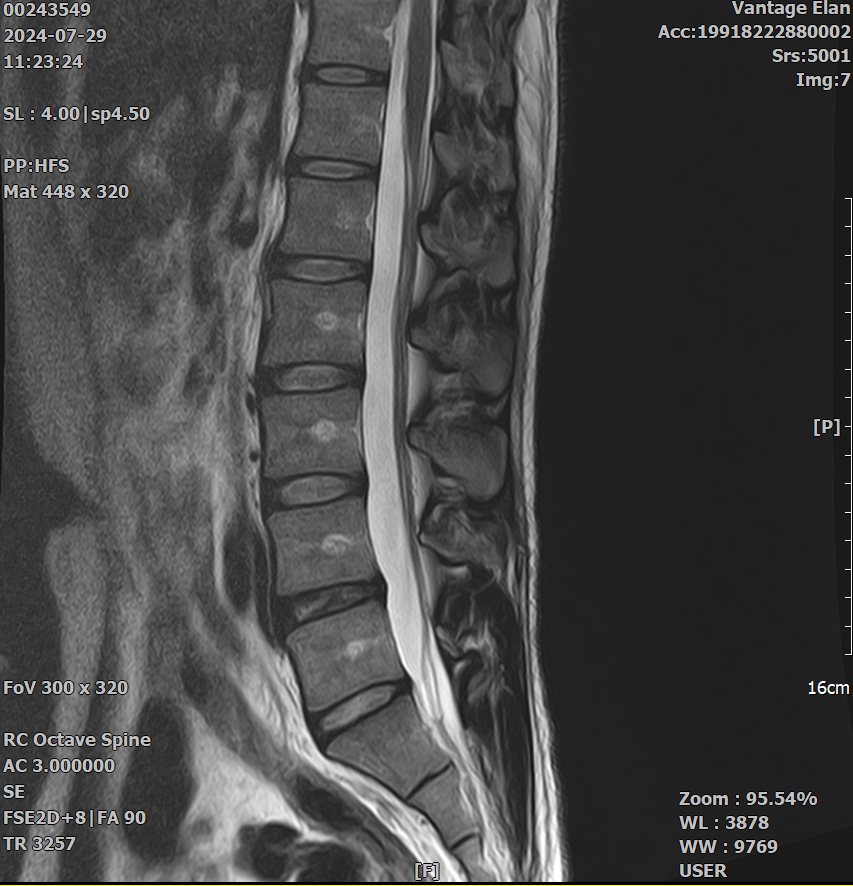

두가지 증상 때문에 요추와 골반 MRI 를 촬영하게 되었습니다.

저는 각기 다른 질환 (고관절충돌증후군과 척추관협착증) 을 의심하였는데 병원에서는 모두 허리디스크 퇴행으로 인한 것이라고만 설명해서 실제로 다른 가능성은 없는것인지 궁금하여 질문 남깁니다.

아래 영상 첨부하였지만.. 이정도 상태로 아래와 같은 두가지 증상이 생기는 것이 상식적인 이야기인지 궁금합니다. (골반 영상은 무엇을 첨부해야할지 몰라 첨부하지 않았지만 영상상으론 아무 문제 없다고 들었습니다.)

평상시에 1시간씩 빠른 속도로 걷는 것을 즐겨하고 산책도 좋아하는 편인데, 유독 느린 템포로 가다 서다 반복하는 경우에 시간이 얼마 지나지 않아 허리가 끊어질것 같은 느낌이 듭니다. 심하면 집을 나선지 30분도 안되어 통증이 발생하여 점점 심해집니다. 눕거나 쪼그려 앉으면 바로 증상이 바로 완화되고, 앉아서 등을 기대면 괜찮아지기도 합니다. (디스크로 인한 문제보다는 척추관협착증과 관련있지 않나 의심)

우선 mri와 질문하신 내용들을 종합해봤을때 증상으로는 충분히 고관절충돌증후군 또는 고관절활액막염이 의심이 가는 증상이고, 척추관협착증에서 나타나는 증상이기도 합니다 (빠른 시일내에 호전을 보이셨기에 이 부분은 확인 해보셔야 할것 같습니다).

다만 mri상 허리 척추 뼈와 뼈 사이의 공간은 협착증이 심해 보이진 않고 다만 퇴행성의 모습이 보이기도 합니다.